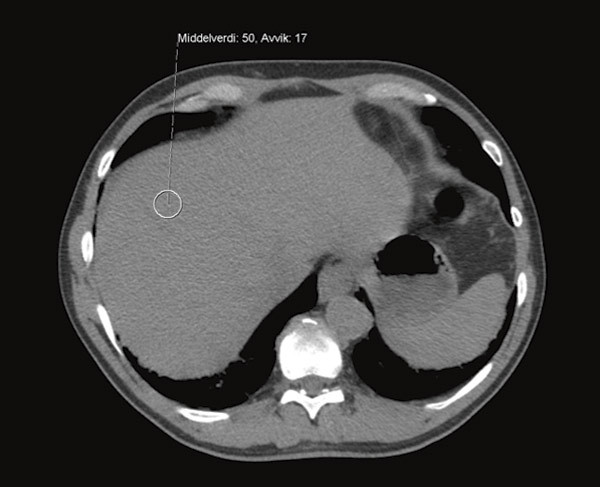

Det ble utført CT-undersøkelse av leveren, som viste patologisk forhøyet signal med gjennomsnittlig tetthet 100 HU (Hounsfield Units) (fig 2, fig 3), klart forenlig med jernavleiring i lever. På bakgrunn av dette ble sannsynligheten for toksisk oppladning i leveren vurdert som så stor at risikoen ved en leverbiopsi ikke var rettferdiggjort. Det ble også gjort MR cor ved universitetssykehuset, der T2-vektet bilde viste maksimalt patologiske verdier på < 10 ms (> 20 ms), forenlig med jernavleiring i myokard (fig 4). Vi fant ingen validert måte å måle jernavleiring i pancreas og thyreoidea på.